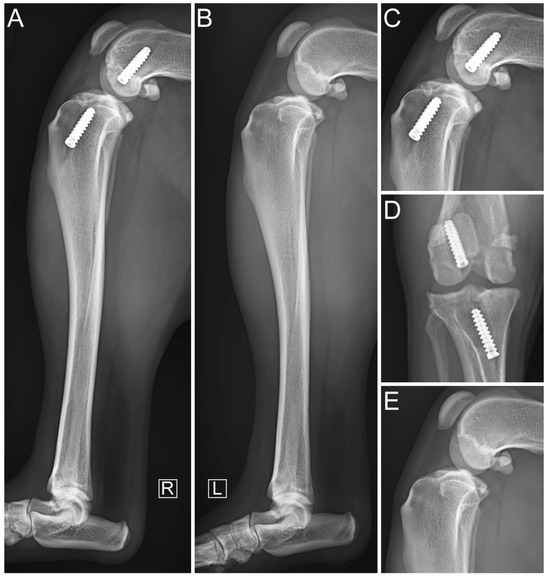

2.3. Diagnostic Imaging under Anesthesia

2.5. Immediate Postoperative Evaluation